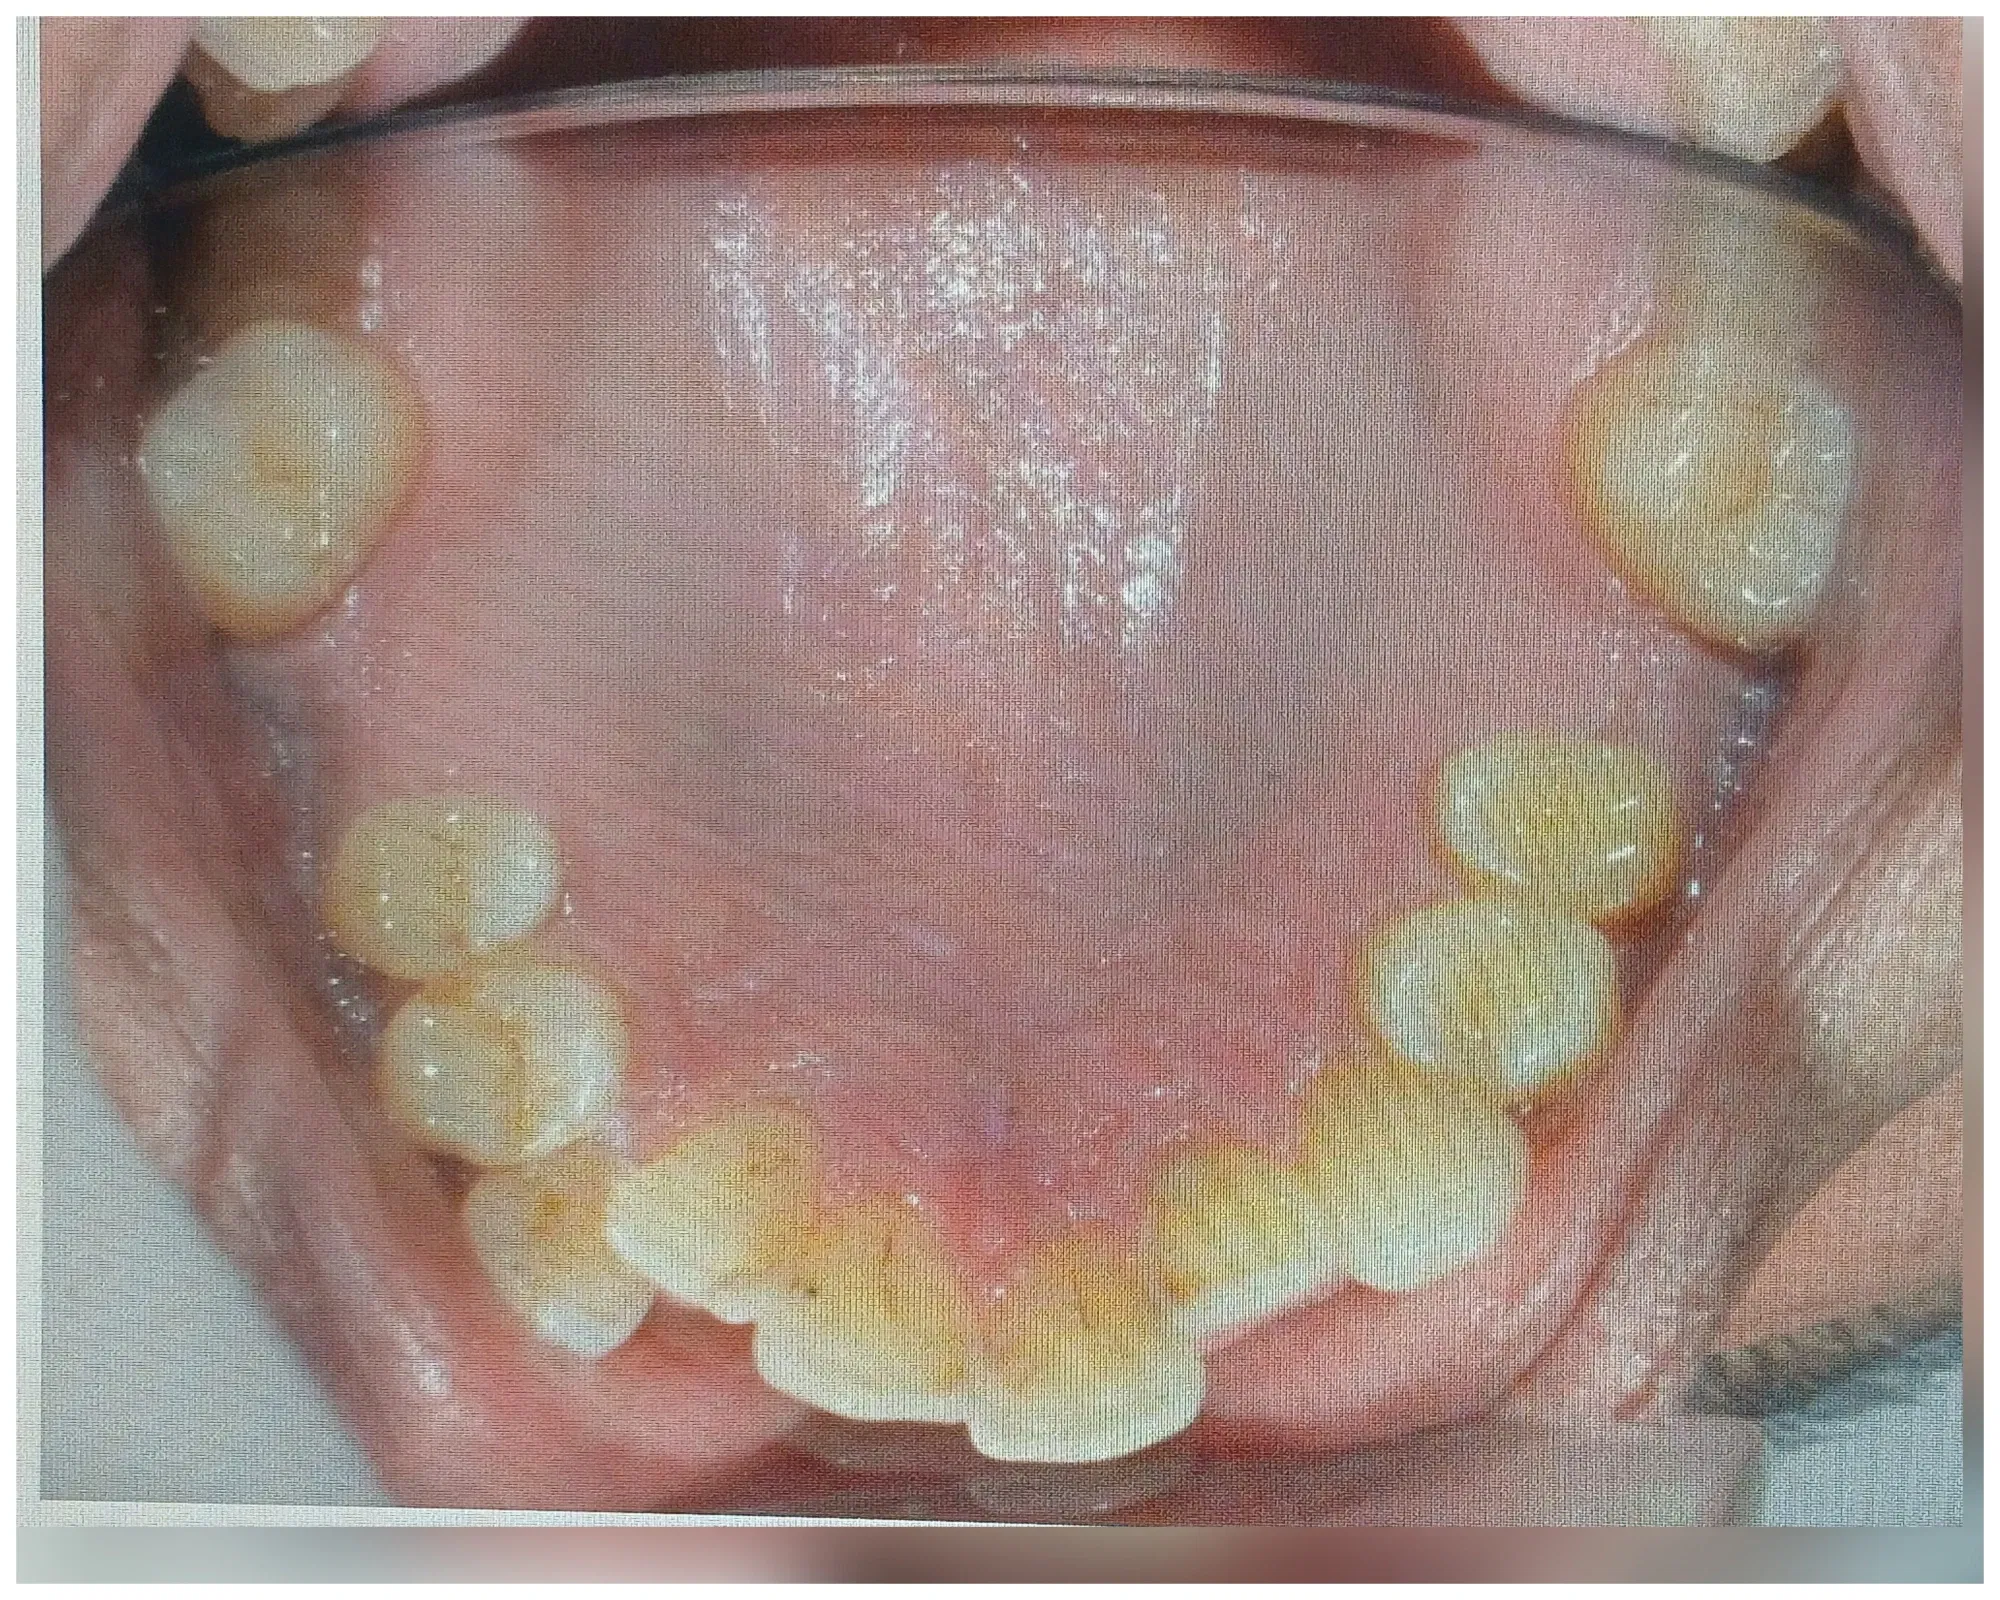

el apiñamiento dental es una condición donde los dientes no tienen el suficientemente espacio para poder tener una oclusión perfecta esto se puede deber a que hay poco espacio los maxilares al momento de la erupción dentaria de los dientes permanentes puede tener distintas causas las tres principales son hábitos con Factor genético y el tipo de alimentación.

Podemos aplicar brevemente cada uno de ellos los hábitos tenemos como el hábito de respirador bucal o el destrucción digital de chupar deo o el del chupete o chupón no puede causar una malformación en desarrollo de los maxilares que los puede contraer por lo tanto al momento del recambio dentario cuando vienen los dientes permanentes pues son mucho más grandes y el espacio está reducido en cuanto a la alimentación tenemos que en tiempo de nuestros abuelos y bisabuelos pues la alimentación de ellos era mucho más magra la era una comida menos refinada por lo tanto ellos tenían que utilizaban más la mandíbula y los dientes para triturar para mascar para rasgar ya hoy en día Todo se le da listo picado al niño Entonces no hace ningún tipo de esfuerzo para estimular el desarrollo tanto óseo como muscular lo que provoca también contracción en los maxilares.

Por último y él no menos importante es una condición genética donde un niño puede heredar el tamaño óseo del papá y el tamaño dental de la mamá o viceversa aquí eso también contribuye a que de repente tengamos un maxilar pequeño en dientes muy grandes o maxilar grande diente muy pequeño dependiendo de la genética o de la herencia que deje cada uno los progenitores.

En cualquiera de los casos pues hay que realizar un tratamiento ortopédico si son niños y tratamiento ortodoncia en el futuro para alinear los dientes y nivelarlos y hacerles el espacio suficiente en el arco dental para tener una mordida excelente para no tener trauma de oclusión ni alteraciones en el artículo Centre por mandibular esto cuando entre más temprano se puede realizar este tipo de tratamiento pues mucho mejor cualquier duda comentario pregunta o interconsulta estoy muy dispuesta alegre de poderte ayudar y responder.